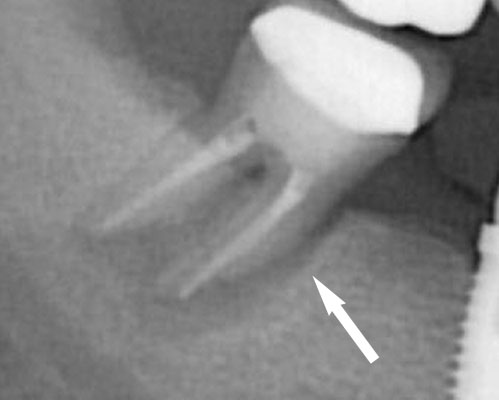

歯の根に亀裂が入った 歯が割れたりヒビが入ったりすると歯ぐきが腫れます。症状は歯周病と似ているのですが、歯周病と異なり数日で改善する事はなくずっと歯ぐきの腫れた状態が続きます。そして、多くは噛むと違和感や痛みを感じます。時間が経つとレントゲンで歯の周囲に帯状に影ができますが、初期では正常像で確定診断することは非常に難しいケースです。